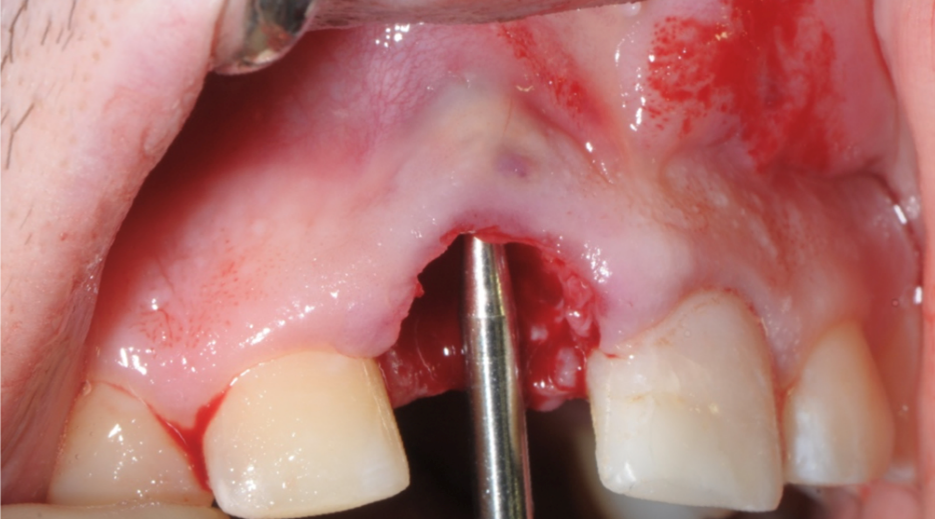

Evidenza clinica della mancanza di parete vestibolare

Inserimento della membrana in dPTFE Cytoplast TXT 1224 tramite sutura e posizionamento di sostituto osso suino ad alta porosità Zcore™.